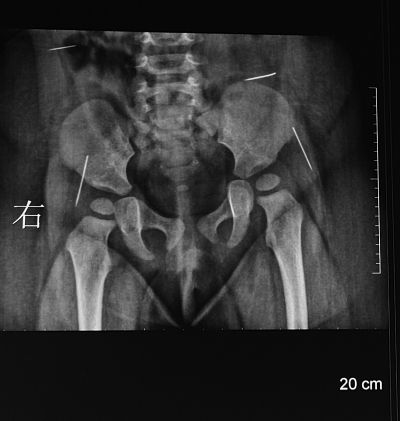

X片顯示,萌萌體內有四根針狀金屬物。

陳醫生告訴記者,看著襁褓里哭鬧不已的女嬰,他首先對女嬰進行初步檢查,發現她的臀部有一明顯的針眼,而且有點感染,后經女嬰父母介紹他才得知,7月22日,由于萌萌一直哭鬧,家人在她的臀部發現一根沒有針鼻的縫衣針,于是送到淮安市第一人民醫院將這根冒出體外的縫衣針給拔掉了,該院也為女嬰拍了一次X片,X片顯示女嬰體內還有四根針狀金屬物,醫院建議到婦幼保健院做手術。

“有一點是肯定的,這四根縫衣針都是通過外力作用被戳進萌萌體內的”,陳衛兵告訴記者,從取出的縫衣針所附的體液顏色以及縫衣針所處體內位置的感染程度來看,這四根縫衣針在萌萌體內至少一個多月了。在萌萌手術前所拍的CT片上,清晰可見四個白亮亮長短不一的縫衣針,所處的位置分別在腰部和臀部兩側。陳衛兵告訴記者,臀部的兩根縫衣針非常危險,已經移動到髖關節之間,有可能觸及萌萌的坐骨神經,處于腰部的那根更危險,因為眼看著就要移動到肝臟位置。